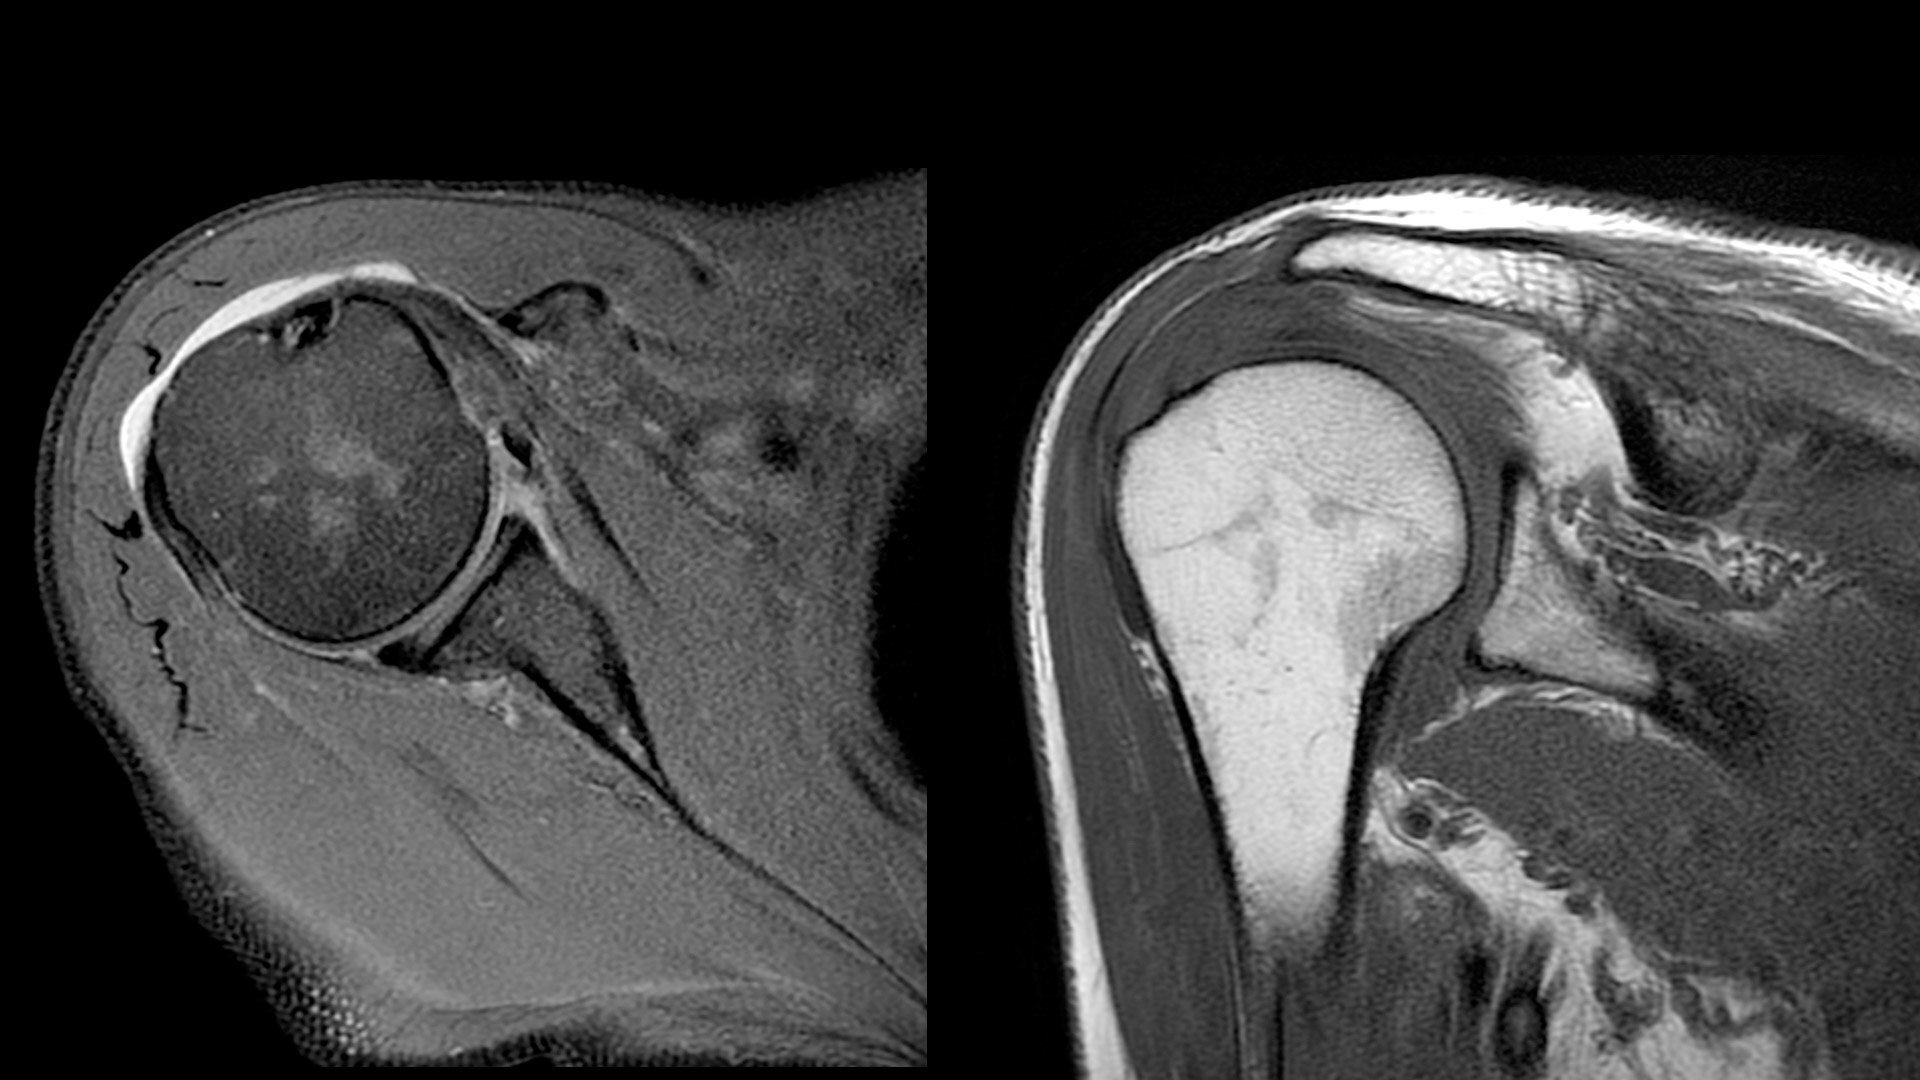

An award-winning industry first in MRI coils. With overlapping, ultra-light, flexible coil elements at their heart, AIR™ Coils deliver an MRI experience that gets closer to your patient, so you get closer to the truth. Representing a new standard in MRI coil technology, AIR™ Coils enable a simplified, faster workflow while maintaining excellent image quality. Scan complex anatomies and complicated conditions in a variety of patient sizes with exceptional results.

The shape of the MRI coil no longer determines what you can do with it. Wrap it around a knee for a complete knee image. Drape it over the patient's body. With an adaptive AIR™ Coil that is light, form fitting and easy to position, it’s the closest you can get to total positioning freedom with 360-degree coverage.

• 360 degrees of coverage for MSK imaging

• 38% lighter per channel compared to previous generations of conventional coil technology

• Increased acceleration compared to previous generations of conventional coil technology

• Positioning freedom with previously hard-to-scan anatomies

• 20-ch and 21-ch design to accommodate all patient sizes and anatomies